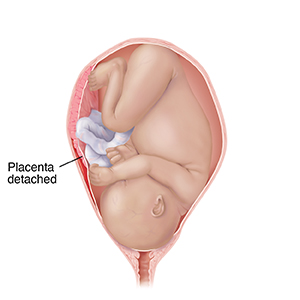

Placental abruption.Placenta separates from the uterus.